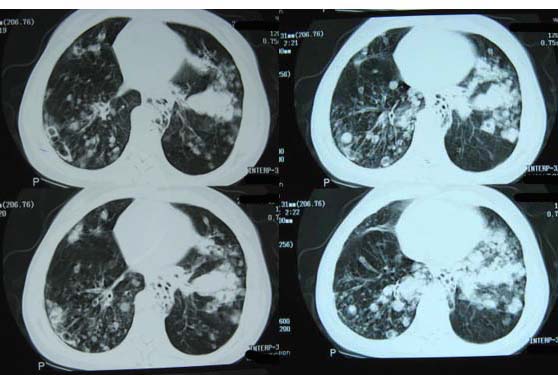

1双肺支气管扩张  2双肺多发块状影,考虑:转移瘤;3肝门区圆形软组织影,先考虑:转移淋巴结可能性大.

期待结果!

1.考虑双肺转移,建议增强ct及纤支镜;

2.双肺肺气肿,支扩伴少许感染;

3.双中上肺陈旧性病灶。